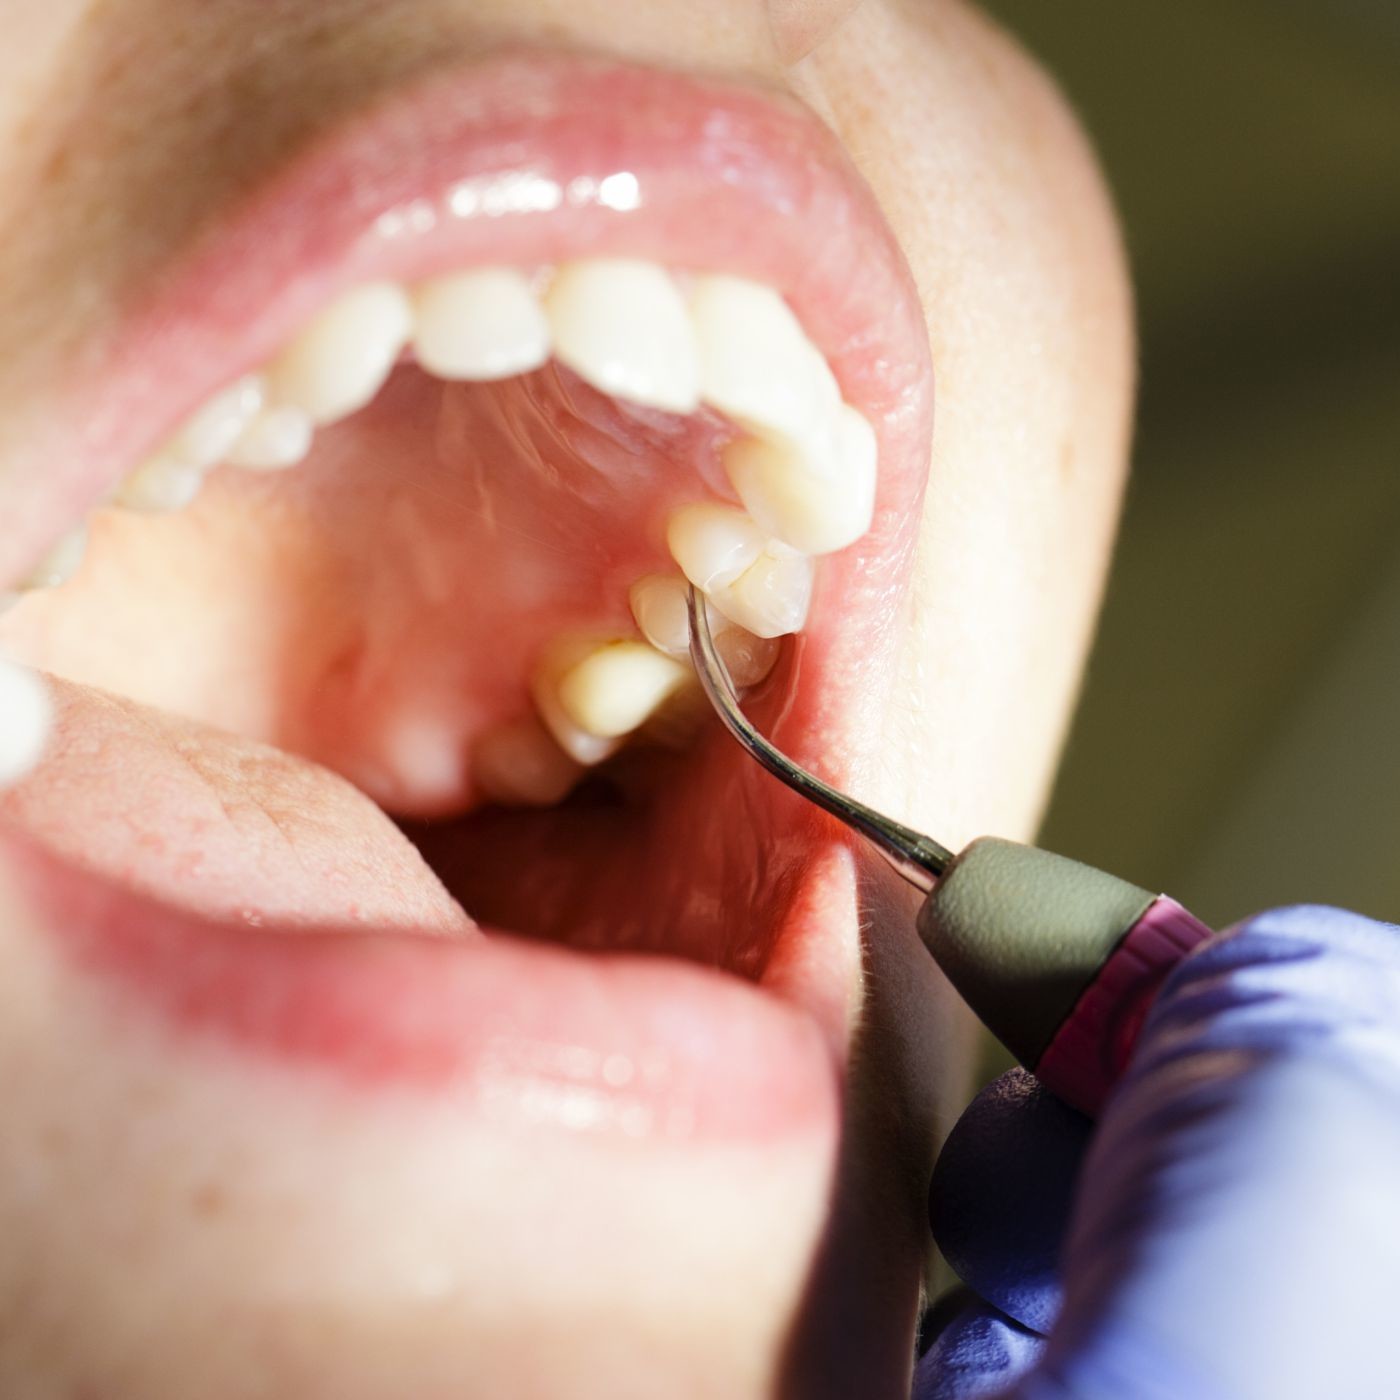

Measuring the Sulcus

Your dental professional may choose to conduct a periodontal screening assessment to determine your risk of developing gum disease. They will take a small ruler, called a periodontal probe, and place the probe just under the gum tissue to measure the pocket depth. The probe enters the gingival sulcus and gently presses against the spot where the gum tissue attaches to the tooth surface. In the sleeve example, it is easy to picture this concept by putting your finger under the cuff of your sleeve.